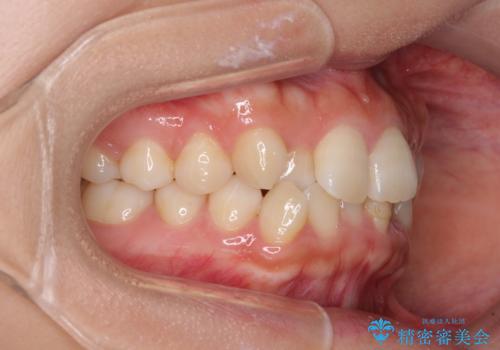

前歯のクロスバイト 目立たないワイヤー装置で速やかに矯正治療

- 前歯のクロスバイトを気にして来院された患者様です。

治療方法としては、マウスピース矯正(インビザライン)でもワイヤー矯正でも、何でも対応可能ですが、自己管理の煩わしさがなく、治療期間の目処を立てやすい表側のワイヤー矯正にて治療を行うこととしました。